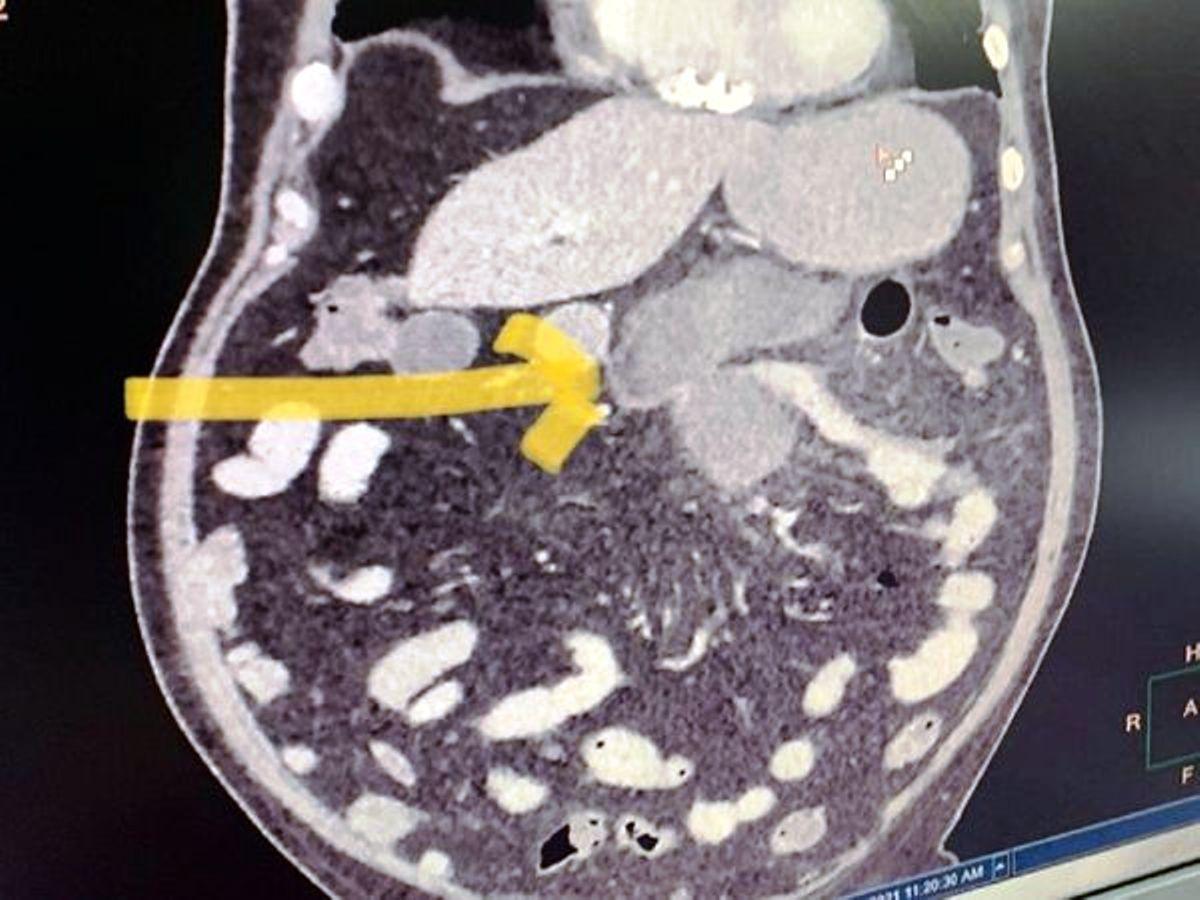

న్యూఢిల్లీ: స్వల్ప కోవిడ్ లక్షణాలున్నవారు సీటీ స్కాన్లు చేయించుకోవాల్సిన అవసరం లేదని, ఎక్స్రే తీస్తే చాలని అఖిలభారత వైద్యవిజ్ఞాన సంస్థ ఎయిమ్స్ డైరెక్టర్ రణదీప్ గులేరియా తెలిపారు. సీటీ స్కాన్ కేవలం కొ�